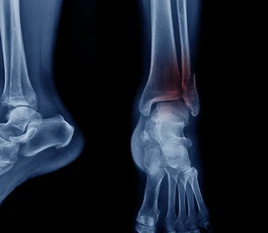

Ankle Fracture Surgery: Understanding the ORIF Procedure

ORIF stands for Open Reduction Internal Fixation. It generally describes fixing a fracture. What is ORIF surgery? ORIF surgery is a surgical procedure where an incision is made to open the joints to expose any fracture and to then fix that with either plates or screws, or a combination with plates. Why ORIF surgery is […]